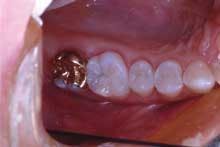

A 30-year-old female presents all four quadrants of her posterior teeth with amalgam restorations in varying degrees of functionality (Figure 1).

Tooth No. 2 has a large amalgam and the distal-lingual cusps test positive for a fracture. Tooth No. 3 has two large amalgams and recurrent decay. Tooth No. 4 has some marginal breakdown and has recurrent decay distally. Tooth No. 5 has some minor marginal breakdown.

The patient is presented a treatment plan to restore this quadrant of teeth. As each of her other posterior quadrants show similar restorative dentistry, a treatment plan is created quadrant-by-quadrant. Each quadrant is prioritized in the development of the treatment plan.